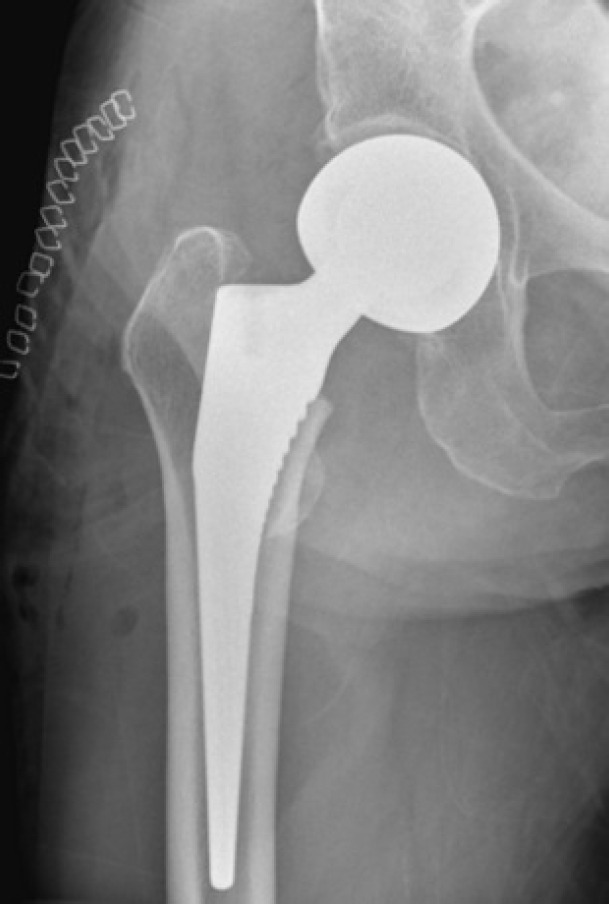

股骨颈骨折常见于老年患者,通常需要手术干预以迅速恢复活动能力并减少并发症。虽然前路、外侧路和后路常用于半关节置换术,但每种入路都有其优缺点。值得注意的是,在一些研究中,后路入路与较高的脱位风险有关。SPAIRE(保留梨状肌和内肌,修复外肌)技术是传统后外侧入路的现代适应。这种微创、解剖上考虑周到的方法保留了梨状肌肌腱和上孖肌、闭孔内肌和下孖肌的联合肌腱。然而,它需要切开闭孔外肌的肌腱。该技术旨在保持肌肉结构稳定,降低脱位风险,加速功能恢复,包括神经系统疾病患者。本病例报告描述了一名79岁女性右股骨颈经颈骨折的治疗。采用SPAIRE技术行双极半关节置换术。该手术有效地保留了梨状肌-关节肌腱(股四头肌髋)的功能协同单位,并包括细致的包膜和肌腱修复。患者术后恢复的特点是在3个月的随访中功能预后良好。本病例强调了SPAIRE技术在增强关节稳定性和促进快速恢复方面的优势,特别是在老年患者中。

Femoral neck fractures commonly occur in older patients and typically require surgical intervention to promptly restore mobility and minimize complications. While the anterior, lateral, and posterior approaches are frequently employed for hemiarthroplasty, each has its own benefits and drawbacks. Notably, the posterior approach has been linked to a higher risk of dislocation in some studies. The SPAIRE (saving piriformis and internus, repair of externus) technique is a modern adaptation of the traditional posterolateral approach. This less invasive, anatomically considerate method preserves the piriformis muscle tendon and the conjoint tendon of the superior gemellus, obturator internus, and inferior gemellus muscles. However, it involves sectioning the tendon of the obturator externus muscle. The technique is designed to maintain stabilizing muscular structures, decrease dislocation risk, and hasten functional recovery, including in patients with neurological conditions. This case report describes the treatment of a 79-year-old woman with a transcervical fracture of the right femoral neck. A bipolar hemiarthroplasty was performed using the SPAIRE technique. The procedure effectively preserved the functional synergistic unit of the piriformis-conjoint tendon (quadriceps coxa) and included meticulous capsular and tendinous repair. The patient's postoperative recovery was characterized by an excellent functional outcome at the 3-month follow-up. This case highlights the advantages of the SPAIRE technique in enhancing joint stability and facilitating rapid recovery, especially in geriatric patients.